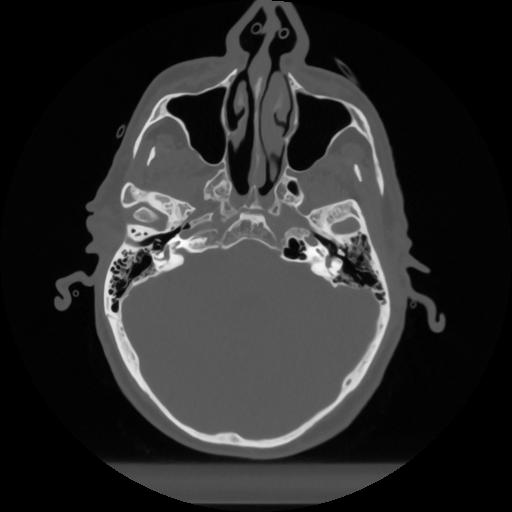

12 P.BLANDAS,,Vol,0.5,P.BLANDAS,,